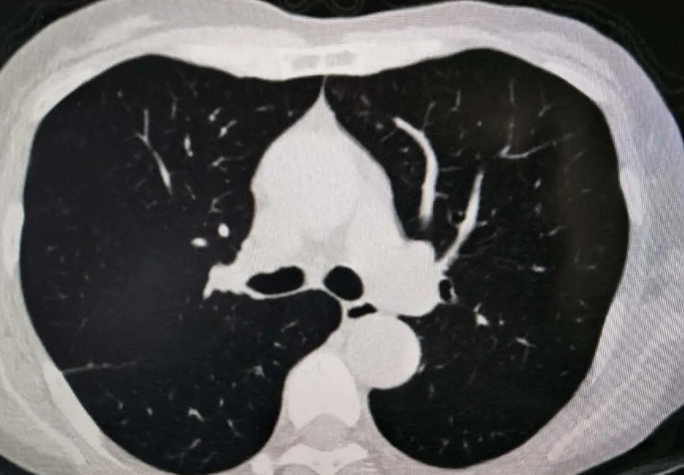

发现磨玻璃结节后该怎么办?

1.对于孤立的,直径<5mm的纯磨玻璃结节患者可不随访,特别是年老的患者。这种磨玻璃结节在病理上多属于不典型增生,少数为原位癌,而磨玻璃结节的倍增时间很长,不典型增生的倍增时间长达2.7年,原位癌也要1.5年,因此对于年老的患者来说可以不用随访。

2.对于孤立的直径> 5mm的纯磨玻璃结节患者,在发现结节后3个月需复查,看是否为一过性结节(可能是感染所致)。如果病变持续存在,至少3年内有必要每年复查。这种大小的病变多为不典型增生、原位癌和少量微浸润性腺癌。不建议患者使用抗生素和CT引导穿刺,因为病灶太小,无法得到病变组织,阳性率低。如果随访期间病灶增大或CT密度增加,可以进行手术。

3.对于孤立性和部分实性磨玻璃结节,如果实性成分>5mm,应在发现病变后3个月复查。如果病变持续不变,或者病变变大,就要考虑恶变的可能,尽早手术。

4.如果肺部多发结节为纯磨玻璃结节,部分病灶>5mm,建议3个月后复查。如无变化,应每年复查一次,随访至少3年。